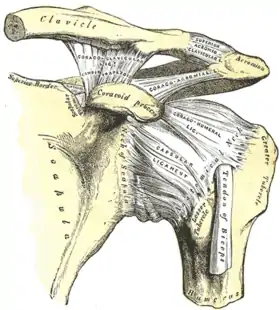

Diagram of the human shoulder joint, back view The left shoulder and acromioclavicular joints, and the proper ligaments of the scapula

The left shoulder and acromioclavicular joints, and the proper ligaments of the scapula Dissection image of the coracohumeral ligament of the glenohumeral joint in green